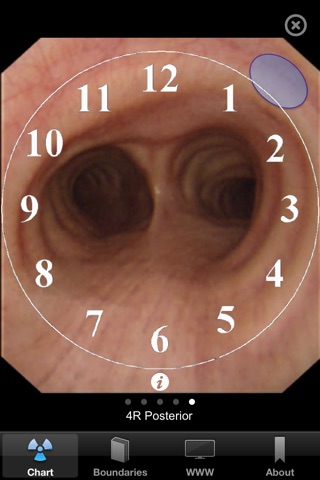

Transbronchial needle aspiration (TBNA) is an important technique for bronchoscopists. Although endobronchial ultrasound transbronchial needle aspiration (EBUS) is more sensitive overall, TBNA is still recommended for patients with bulky mediastinal lymphadenopathy. In addition TBNA is cheaper and faster than EBUS and can be performed during a normal flexible bronchoscopy. To master the art of TBNA extensive knowledge of the bronchial and mediastinal anatomy is required, as well as the necessary skills for adequate lymph node sampling. For novices it is especially difficult to determine the right location to sample a lymph node. The TBNA app is designed to familiarize you with a concept that is easy to apply and will help you to determine the right location in any patient. Central in the TBNA app is the mediastinal and hilar lymph node map. When tapping one of the lymph node stations a sequence of CT and bronchoscopy images is shown. This sequence of five images will take you from the CT scan to the actual bronchoscopy images step by step. A second tab boundaries shows you the boundaries of the lymph node stations on the map.